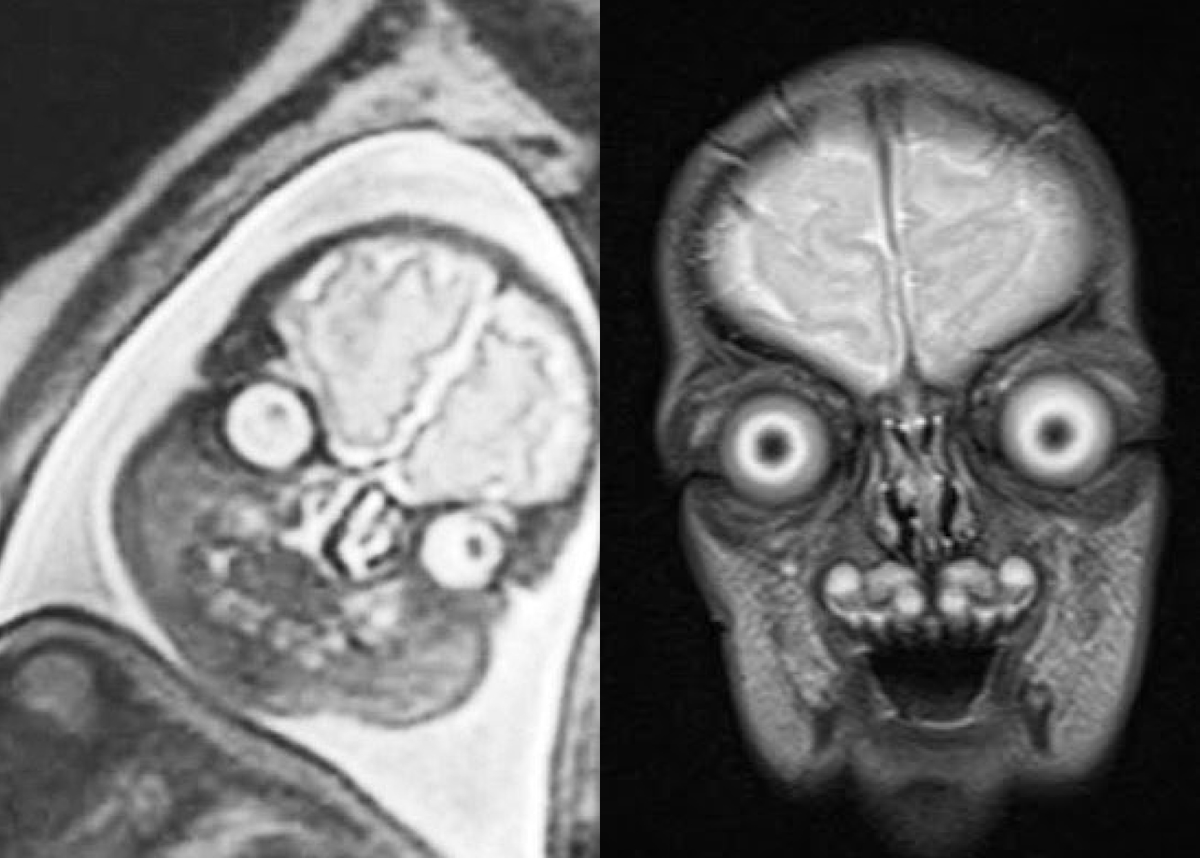

Прошло некоторое время и помощь с МРТ понадобилась моему близкому родственнику, срочно нужно было сделать МРТ перед походом на следующий день в очень серьезный институт на консультацию к нейрохирургу в связи с имеющейся аденомой гипофиза, которая была выявлена в феврале в крупном государственном медицинском учреждении при проведении МРТ.

А в мае после проведения очередного МРТ выяснилось, что аденома уменьшается, как последствия микроинсульта. Так пояснили специалисты.

По результатам МРТ головного мозга, я получила заключение, в котором.... не было ни слова об аденоме. Напомню, собственно именно по этому вопросу мы и обращались за МРТ и заключением. Конечно мы получили еще и диск, как бывает всегда во всех случаях при проведении МРТ.

Но времени делать консультационный пересмотр в другой медицинской организации уже не было. Я связалась с врачом, который нехотя признал мою правоту и дополнил заключение информацией о том, что аденома обнаружена, но вот размеров её он указывать не стал.

Обратите внимание, увидев выписки, "врач" находящийся на дистанционной диагностике (у многих МРТ центров нет врача на месте) просто взял результаты февраля и без зазрения совести указал именно их. Почему? Просто потому что у него не было информации о майских результатах, где аденома уже уменьшилась. Я так думаю, потому что просто сравнила показатели.

Буквально через 3 дня, мы не пожалев средств отправились в крупный медицинский институт для консультативного пересмотра диска, но там сказали что качество аппаратуры последнего МРТ ужасное и максимум что мне могут написать в заключении, это то что на снимках ничего не видно. Пришлось нам делать МРТ заново, конечно снова платно за 12000 рублей. И вот его результаты: